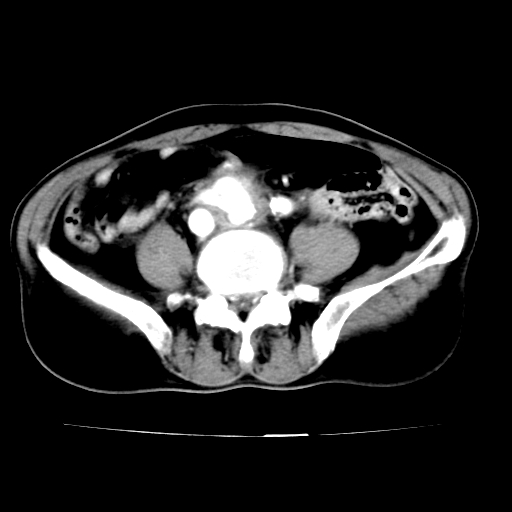

标题: V0243:右髂总动脉瘤附壁血栓形成?破裂?动静脉瘘? [打印本页]

标题: V0243:右髂总动脉瘤附壁血栓形成?破裂?动静脉瘘?

男,75岁,腹痛月余,彩超发现脐周腹主动脉异常回声。临床诊断:腹主动脉瘤。

ct诊断:右骼总动脉囊性动脉瘤并瘤内附壁血栓形成,与下腔静脉之间形成动静脉瘘。

请问各位老师:能排除动脉瘤破裂的可能吗?

各位老师注意到下腔静脉的充盈缺损了吗?注意到动静脉漏了吗?

当时是扫描的标准动脉期,可是下腔静脉与腹主动脉同步强化且幅度一致。所以我想动静脉瘘是存在的。